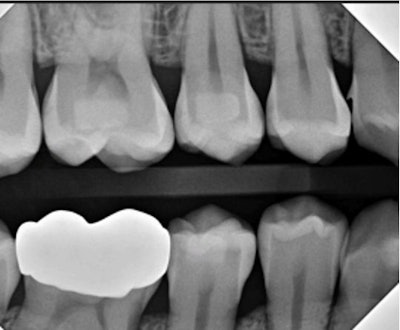

Figure 1: Quick! What’s going on with the distal of #6? It isn’t calculus.Images and captions courtesy of Dr. Ankur Gupta.

Figure 4: The distal surface of #6 now exhibits an underhang.

While I can’t say exactly what happened in this instance, here’s my guess: There was a long, broad contact between #5 and #6, and I was getting more and more uncomfortable as the disc descended into the gingiva, aborting the gingival extension much too early. Rather than confirming smooth interproximal surfaces, I opted for the “I hope this works” technique.